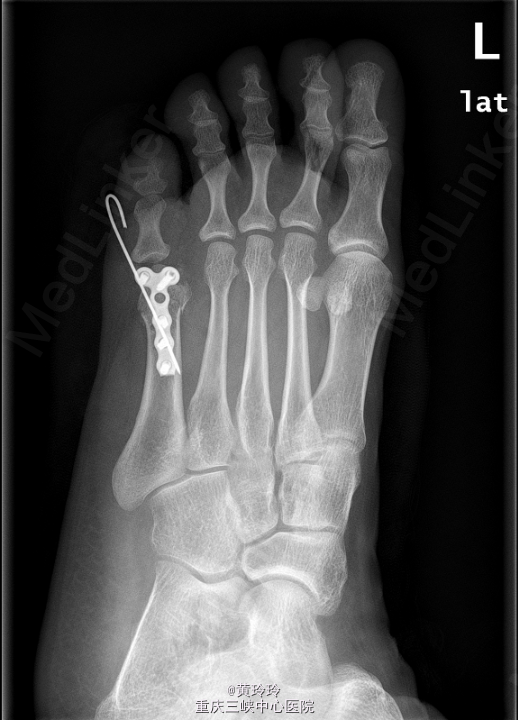

初步诊断:左足多趾畸形.在硬膜外麻醉下行左足多趾截趾加第五跖骨截骨矫形术. 取第5趾两侧切口,保留部分趾蹼皮肤,分离筋膜,去除第五趾。并予第五跖骨远端截骨,截去第五跖骨内侧部分跖骨头,将第六趾移向内侧,接近正常位置,克氏针斜行固定。C臂透视位置可,予T形锁定钢板及螺钉固定。

出院后下肢避免完全负重,避免剧烈活动。术后2周左右拆线。一月后拔除克氏针(具体待X拍片后决定).